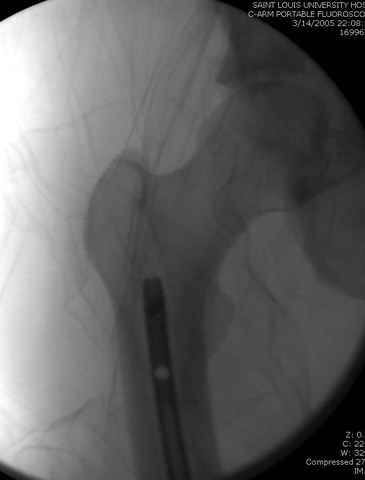

По поводу открытого перелома больной ургентно взят на ретроградное интрамедулярное штифтование, после рутинного дебрайдмента и фасциотомии на бедре и на голени.

интраоперационные

-После мониторинга на компартмент синдром, если давление в компарменте высокое, более 40 мм разницы между диастоличеcким давлением, то фасциотомия.

снимок монитора